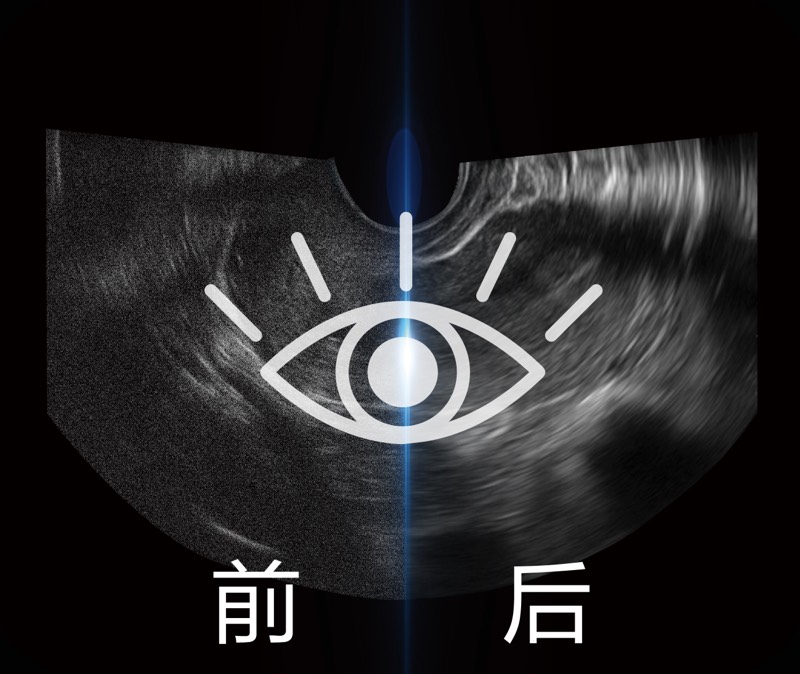

微米成像技术提升了对组织斑点噪声信号的抑制能力,并进一步强化边界信息,从而获得信噪比更优、边界更清楚锐利的图像

随着组织深度的变化,超声接收频率进行智能匹配跟踪,确保图像中、远场良好的穿透力以及整场一致的分辨力,从而得到均一的画质